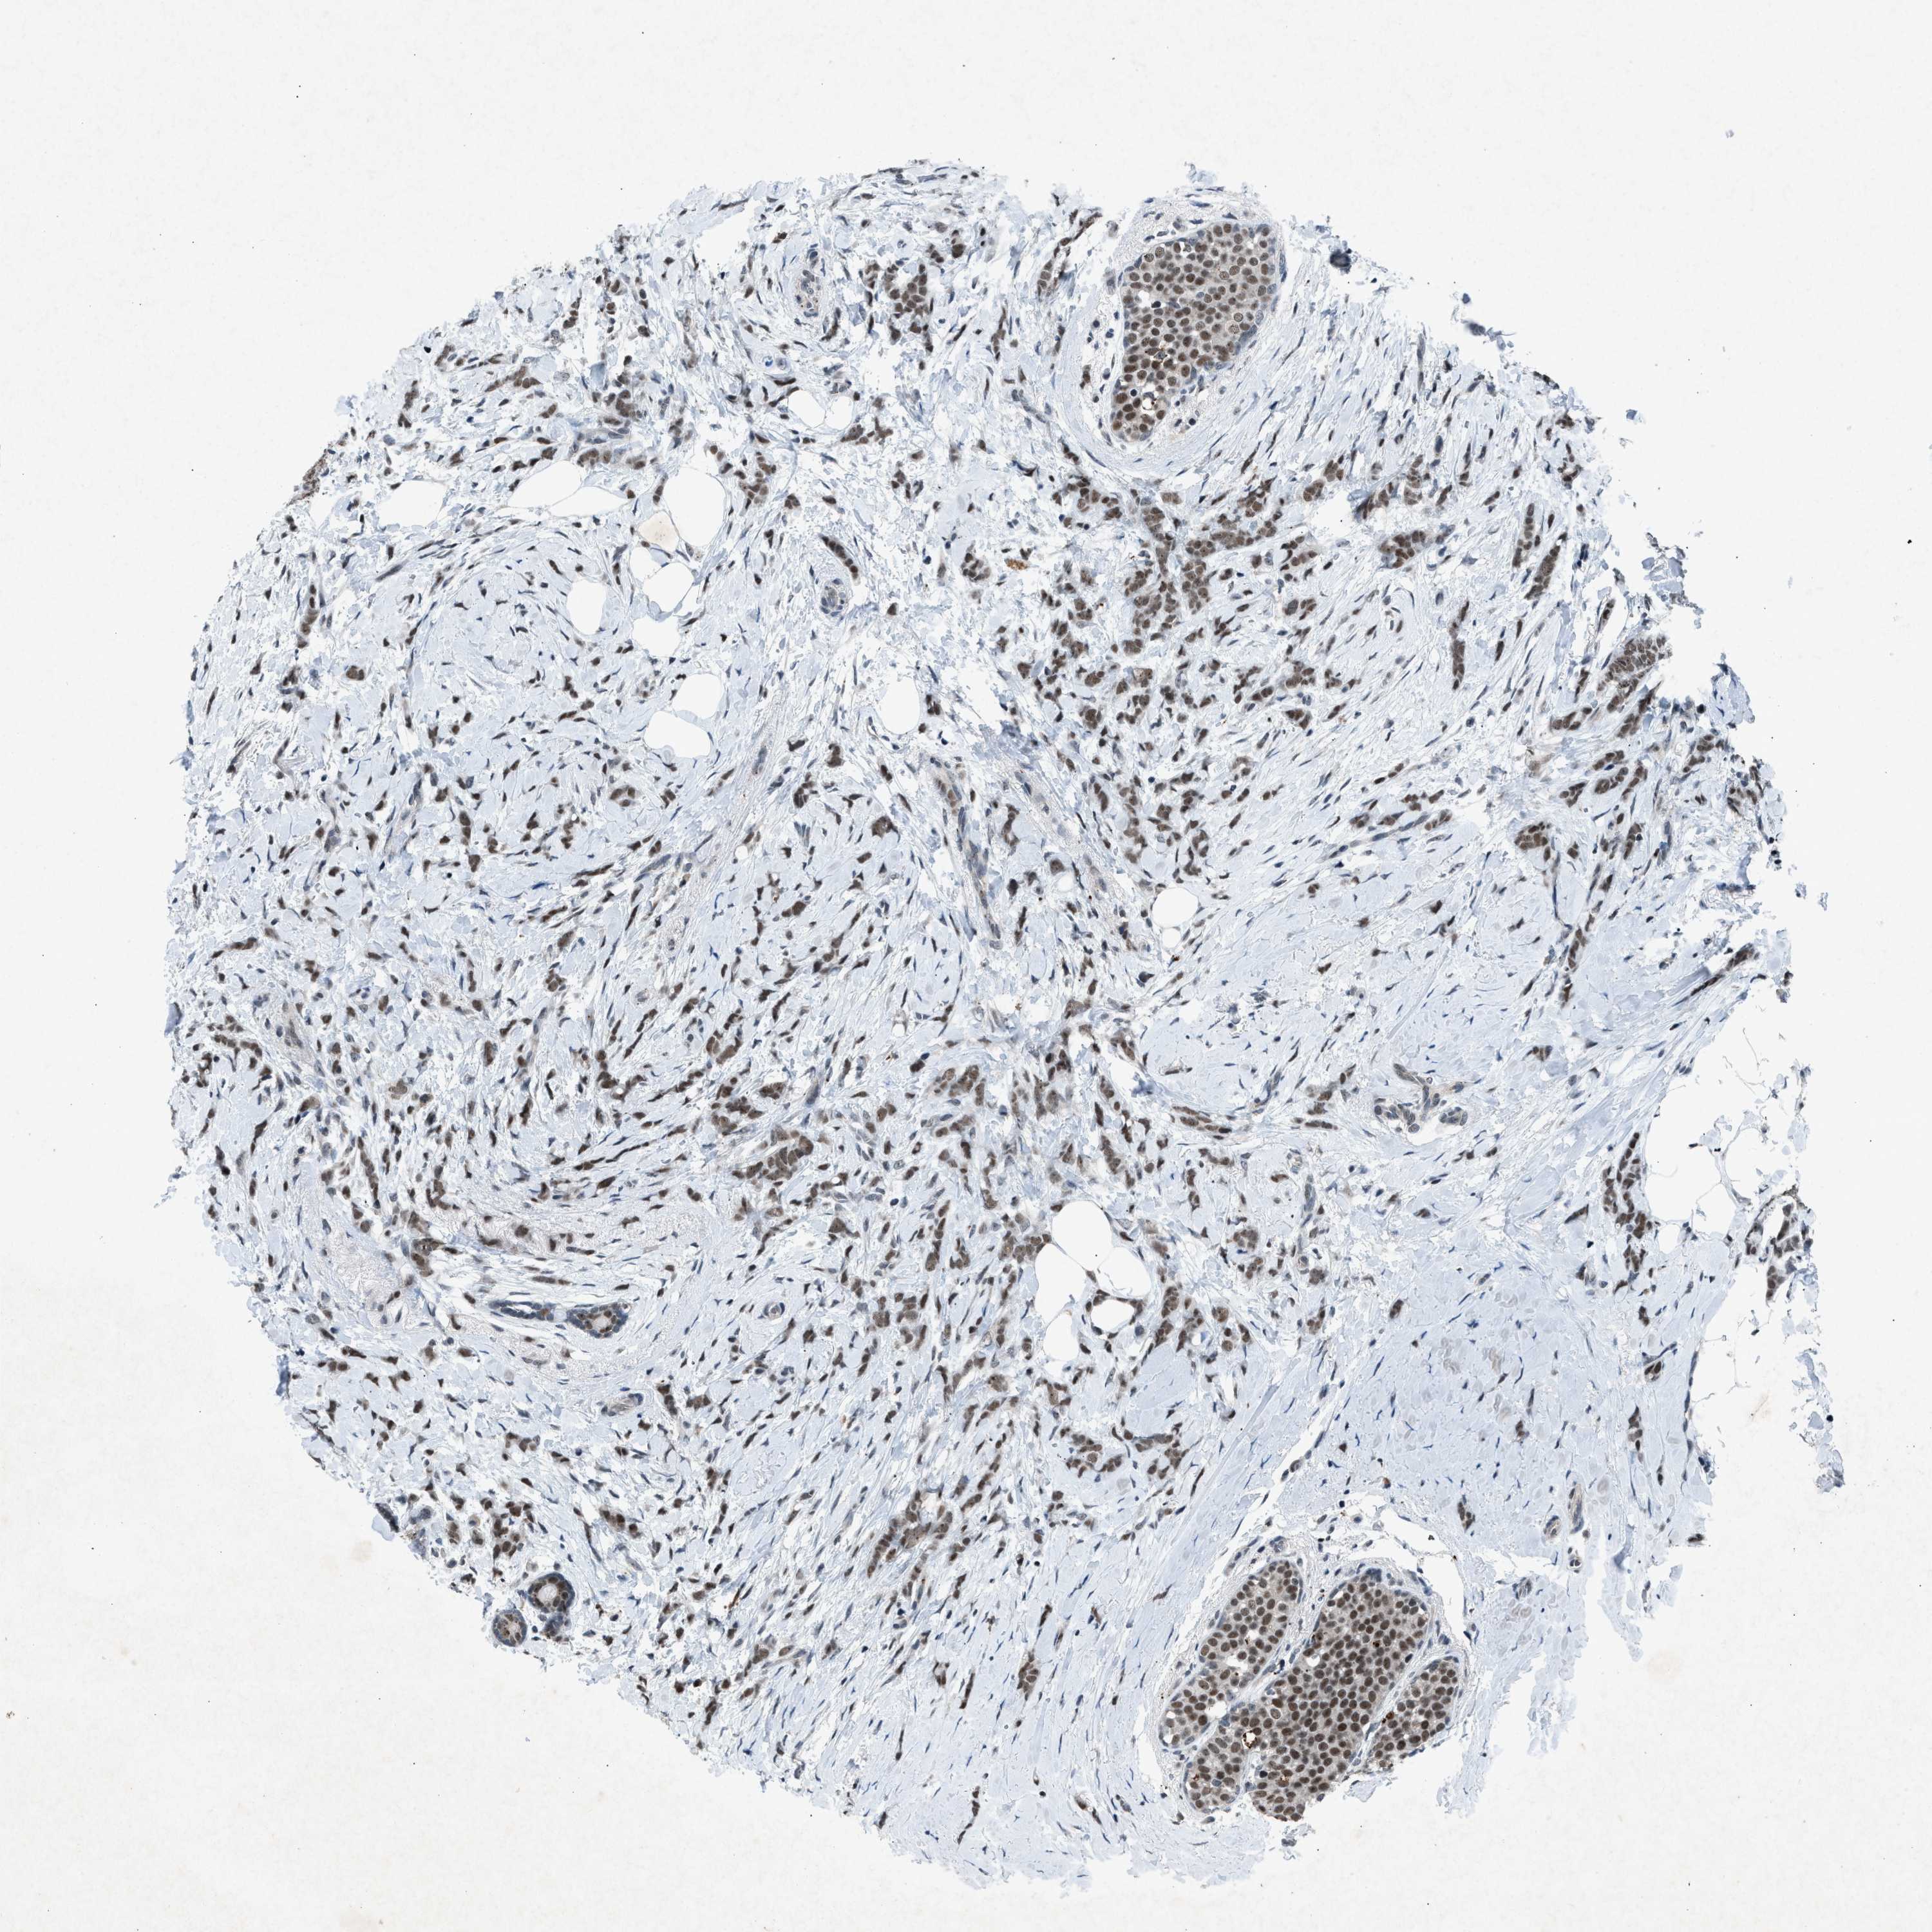

BRCA TCGA BRCA VALIDATION PROTEIN EXPRESSION